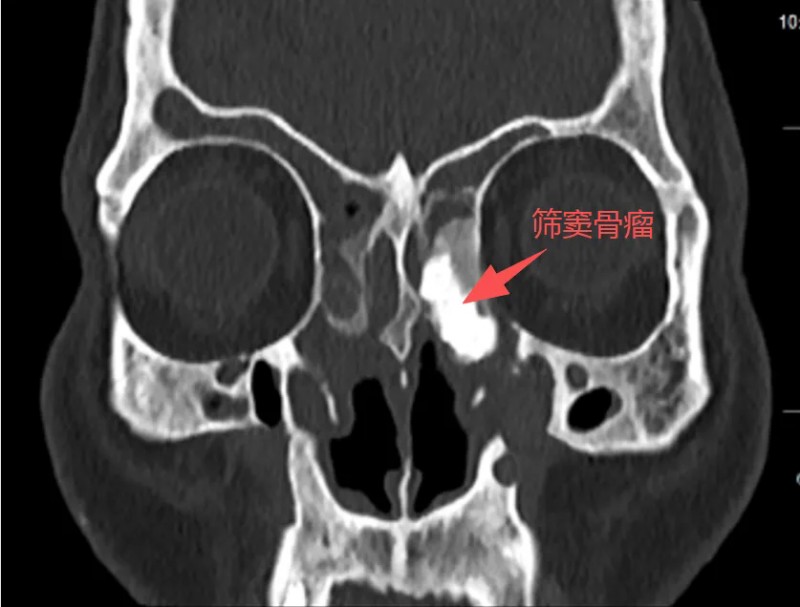

听完病史,王浩心里已经有数。但当他看完影像学检查结果,表情变得凝重起来。张大爷的情况远比普通鼻窦炎复杂得多:双鼻甲肥大,鼻中隔偏曲、鼻道里长满息肉样新生物。最棘手的是左筛窦发现一个巨大占位——高度怀疑是骨瘤,大小约3×4厘米。

术前

“骨瘤本身多为良性,但长在这个位置,就成了一个‘定时炸弹’。”王浩指着影像片子,向患者解释。

筛窦,是鼻腔深处一个结构极其复杂的区域。它的上方是颅底,隔着一层薄薄的骨头就是大脑;外侧是眼眶,视神经、筛前动脉等重要结构都在这里穿行。张大爷的这颗骨瘤,恰恰嵌合在眶内壁上,紧贴着这些要害部位。